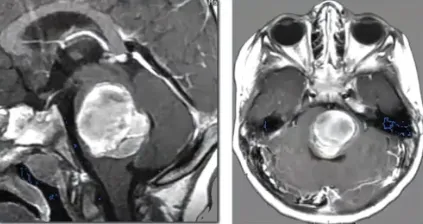

生命的呼吸与心跳,由一颗拇指大小的脑干掌管。这个深藏于大脑底部的生命中枢,由延髓、桥脑和中脑精密构成哪怕一次微小的出血,也可能导致神经功能损伤。 更令人警惕的是,脑干出血...

脑干海绵状血管瘤,这个名字对大多数家庭来说是陌生的。但当一个孩子被确诊时,它带来的恐惧却是实实在在的因为脑干,这个只有拇指大小的结构,掌控着呼吸、心跳、意识、运动,是人体...

女儿苗苗放学回家说头晕,我们以为是流感。周六早上,她突然半边身子动不了了。我是学医药出身的,瞬间就意识到这不是普通的感冒...... 01 晴天霹雳 从流感到半身瘫痪 一切开始得毫无征兆...